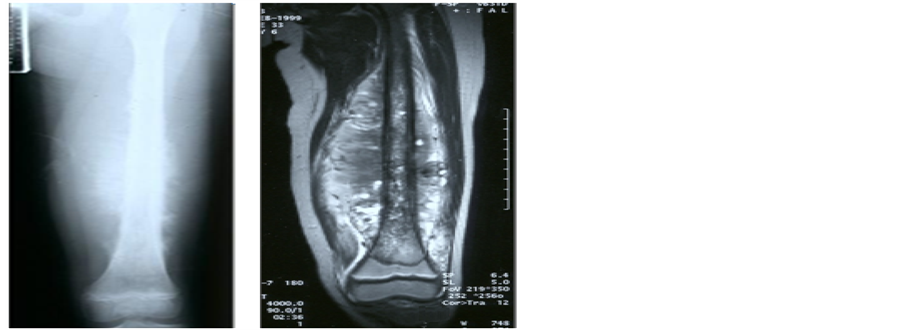

Case 1: (Figure 1(a) and Figure 1(d)) A 7-year-old boy. Osteo-Fibrous Dysplasia (OFD) (A case of tumor excision, LFG, first, and allograft for late recurrence).

This boy slipped down and was broken his right tibia. It was pathologic fracture induced by anterior bowing, shin splint and poly-ostotic cysts on tibia shaft for last 2 years, not treated (Figure 1(a)). The LFG from opposite fibula after wide excision of whole tibia was done (Figure 1(b)). One year after LFG, the grafted fibula was united well and hypertrophied, but seems to recur with similar preoperative cystic changes (Figure 1(c)). Two years later, the recurred OFD was re-established. We don’t know yet the exact causes of recurrence in OFD, and all pathologic findings did not give us any evidences of recurrences, but we believe that it’s pathologic characteristics of osteoid and fibroblasts of OFD in

Figure 1. A 7-year-old boy. Osteo-Fibrous Dysplasia (OFD) (A case of tumor excision, LFG, first, and allograft for late recurrence). (a) Poly-ostotic cysts, shin splint with shaft fracture suggesting OFD; (b) LFG from opposite leg after wide excision of affected tibia; (c) One year after the LFG, solid union and hypertrophied grafted fibula but recurred OFD was recurred; (d) 9 months after the allograft after complete excision of tibia, solid bony union was obtained. The end result in 14 years follow-up was good.

which originated multifocally from periosteum and even adjacent soft tissues too, and so inevitable to incomplete excision at the first operation. Complete re-exci- sion of recurred OFD and allograft was done again (Figure 1(d)), and finally obtain the solid bony union on 9 months after allograft and cancellous chip bone grafts together (Figure 1(d)). The end result was good on 14 years follow-up (Table 1).